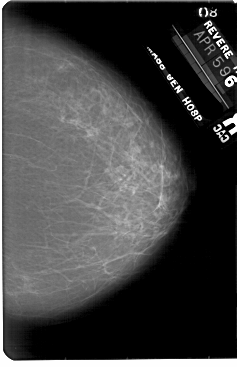

A_1855_1.RIGHT_MLO

RIGHT_CC LINES 5491 PIXELS_PER_LINE 3541 BITS_PER_PIXEL 12 RESOLUTION 43.5 NON_OVERLAY

FILE: A_1855_1.LEFT_CC.OVERLAY

TOTAL_ABNORMALITIES 1

ABNORMALITY 1

LESION_TYPE MASS SHAPE OVAL MARGINS OBSCURED

ASSESSMENT 3

SUBTLETY 3

PATHOLOGY BENIGN

TOTAL_OUTLINES 1

BOUNDARY